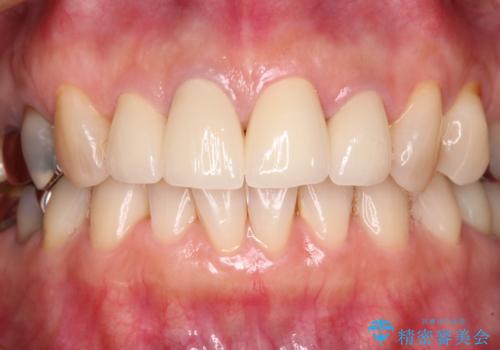

インプラントあるいはブリッジによる補綴治療が考えられましたが、前後の歯が大きな銀歯であったため、オールセラミックブリッジにより3本の歯を審美的に仕上げることとしました。

奥歯の治療をしている間に前歯の治療をどのように勧めるのか検討していただき、最終的には4歯を一度に治療し、審美的に仕上げることとしました。

ブリッジの支台歯は2本とも神経を取り除いている歯であるため、咬合力の強い方ですと、支台歯も歯根破折をするリスクがあります。

今回はそれほど咬合力が強いとは思われなかったため、ブリッジによる補綴治療を行いましたが、念のため、就寝時にはナイトガードとしてマウスピースを装着するようお願いしました。